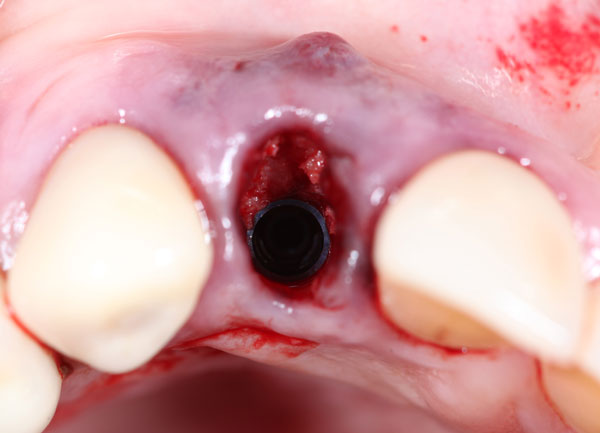

The Immediate Dentoalveolar Restoration (IDR) is a surgical and prosthetical technique established to broaden indications for immediate loading on individual teeth. In this way, tissue losses with varied extensions are reconstructed in the same surgical session of implant placement and provisional crown installation, reducing the number of interventions and keeping predictability on esthetic aspects. The IDR protocol was developed more than 12 years ago from the need to minimize the treatment time

In the course we discuss the scientific basis, the step-by-step technique, indications and bone biology. The IDR technique, which advocates minimally invasive surgery, flapless procedures, is presented as a viable and reproducible alternative.

It is presented several cases, which showed one or more compromised socket walls of the tooth involved, with or without changes of the gingival margin, some with more than 12 years of clinical, radiographic and CT scan follow-up.

Protocol for selection of implant diameter in post extraction sites - A new approach

IDR protocol using cortico-cancellous graft

f. Management of the graft and complete reconstruction of the alveolar defect.